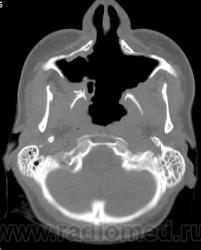

Просьба высказать мнения по поводу представленного патологического процесса.

Кажется, это уже было - гранулематоз Вегенера, если не ошибаюсь.

Гранулематоз Вегенера

Деструктивный процесс в полости носа и в пазухах может представлять собой гранулематоз Вегенера. Требуется тщательное собрание анамнеза, учет клинической картины, и разумеется, биопсия.